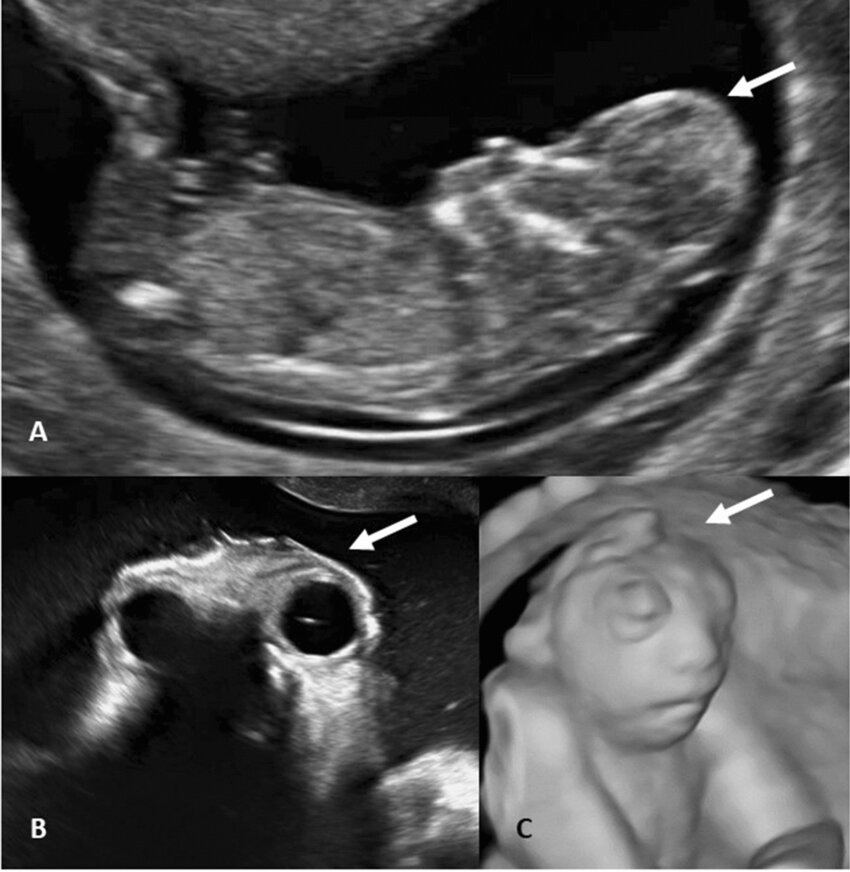

- Evaluation for the presence of multiple gestations

- Early detection of multiple gestations and the determination of chorionicity and amnionicity are crucial for guiding management strategies.

- Screening for fetal anomalies, for example, anencephaly.